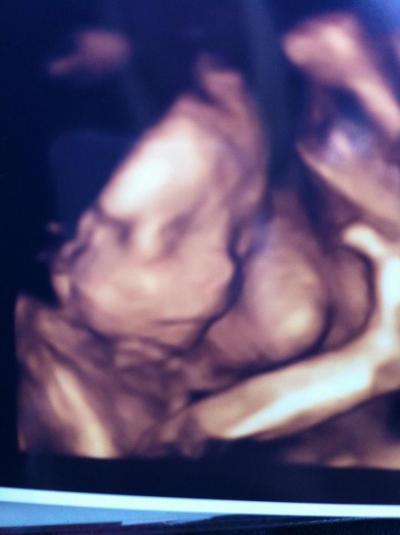

...und ich Reihe mich bei den Jungs-Mamas ein! Alles in bester Ordnung bei unserem Kleinen! Wiegt um die 440g in etwa, Größe weiß ich nicht... Kann es das es ca. 20 cm sind, wenn ic hdas richtig gelesen habe? Kommentare vom FA: "Brilliantes Kerlchen, sehr hübsch & süss - habt ihr super gemacht! Sieht genau aus wie der große Bruder." - Sehr nett und kompetent. Hat mir auch unheimlich meine Angst genommen, habe die Nacht vorher nicht geschlafen weil ich so aufgeregt war. Habe sogar geträumt das es beim Outing ein Junge ist! So viel zu uns!

Bild zu Ebenfalls zurück von der FD! - Forum für Februar - Mamis